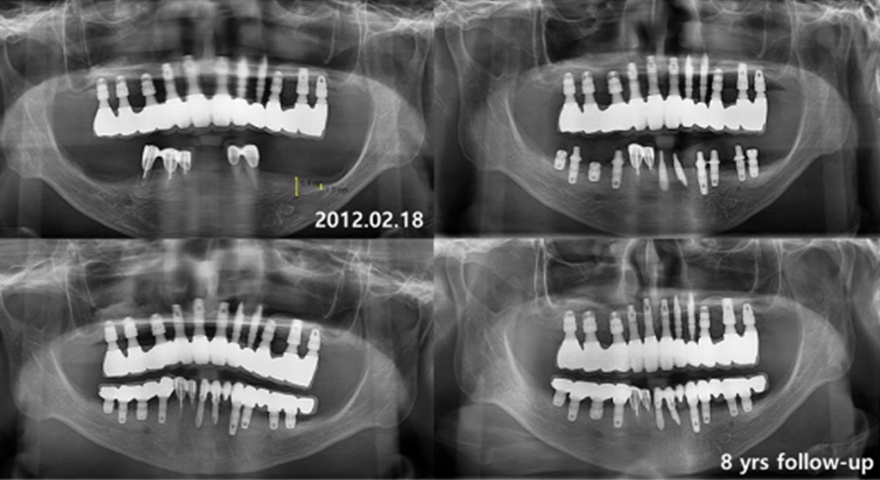

Тотальне протезування на імплантатах INNO (Сowellmedi, Корея)

Пропонуємо вашій увазі відео реального кейсу тотального протезування на імплантатах INNO (Сowellmedi, Корея)

Імпланти встановлені із застосуванням хірургічних шаблонів. Протетична конструкція на гвинтовій фіксації (MUA (Multy Unit Abutment) INNO, Cowellmedi)

Вдячні за кейс лікарю Володимиру Яцуха, клініка Excelline, м. Одеса